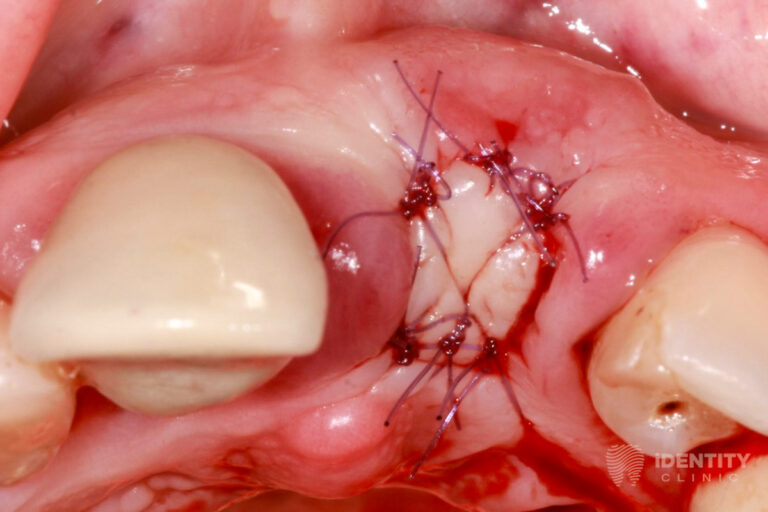

Reménytelen prognózisú 21 (bal felső első) fog eltávolítását követően a nagymértékű csonthiány miatt azonnali csontpótlást végeztünk a páciens saját csontja, illetve kötőszövete segítségével (alveolus prezerváció). Ennek 4 hónapos gyógyulási idejére az eltávolított 21 fog koronáját visszasíneztük a szomszédos fogakhoz. A teljeskörű parodontális terápiát mindeközben elvégeztük.

A bal felső első fog eltávolításával egyidőben csontpótlást (alveolus prezercációt) végeztünk. A sebészi beavatkozás lényege, hogy a fogeltávolítást követően az alveolus (az eltávolított fog helye a csontban) ne essen össze a nagymértékű csonthiány miatt, hanem azt fenntartva a páciens saját csontját és kötőszövetét felhasználva megőrizzük a csontkontúr eredeti formáját.

Mindemellett a gyógyulási idő alatt olyan mennyiségű és minőségű csont képződik az eltávolított fog helyén, melybe implantátum beültetése lehetséges.